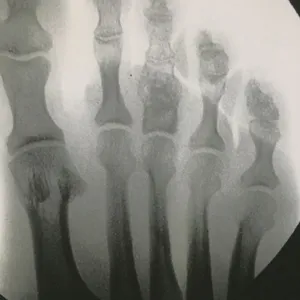

Intraop Pics Of Plantar Medial Foot Release for Chronic Exertional Compartment Syndrome in the foot